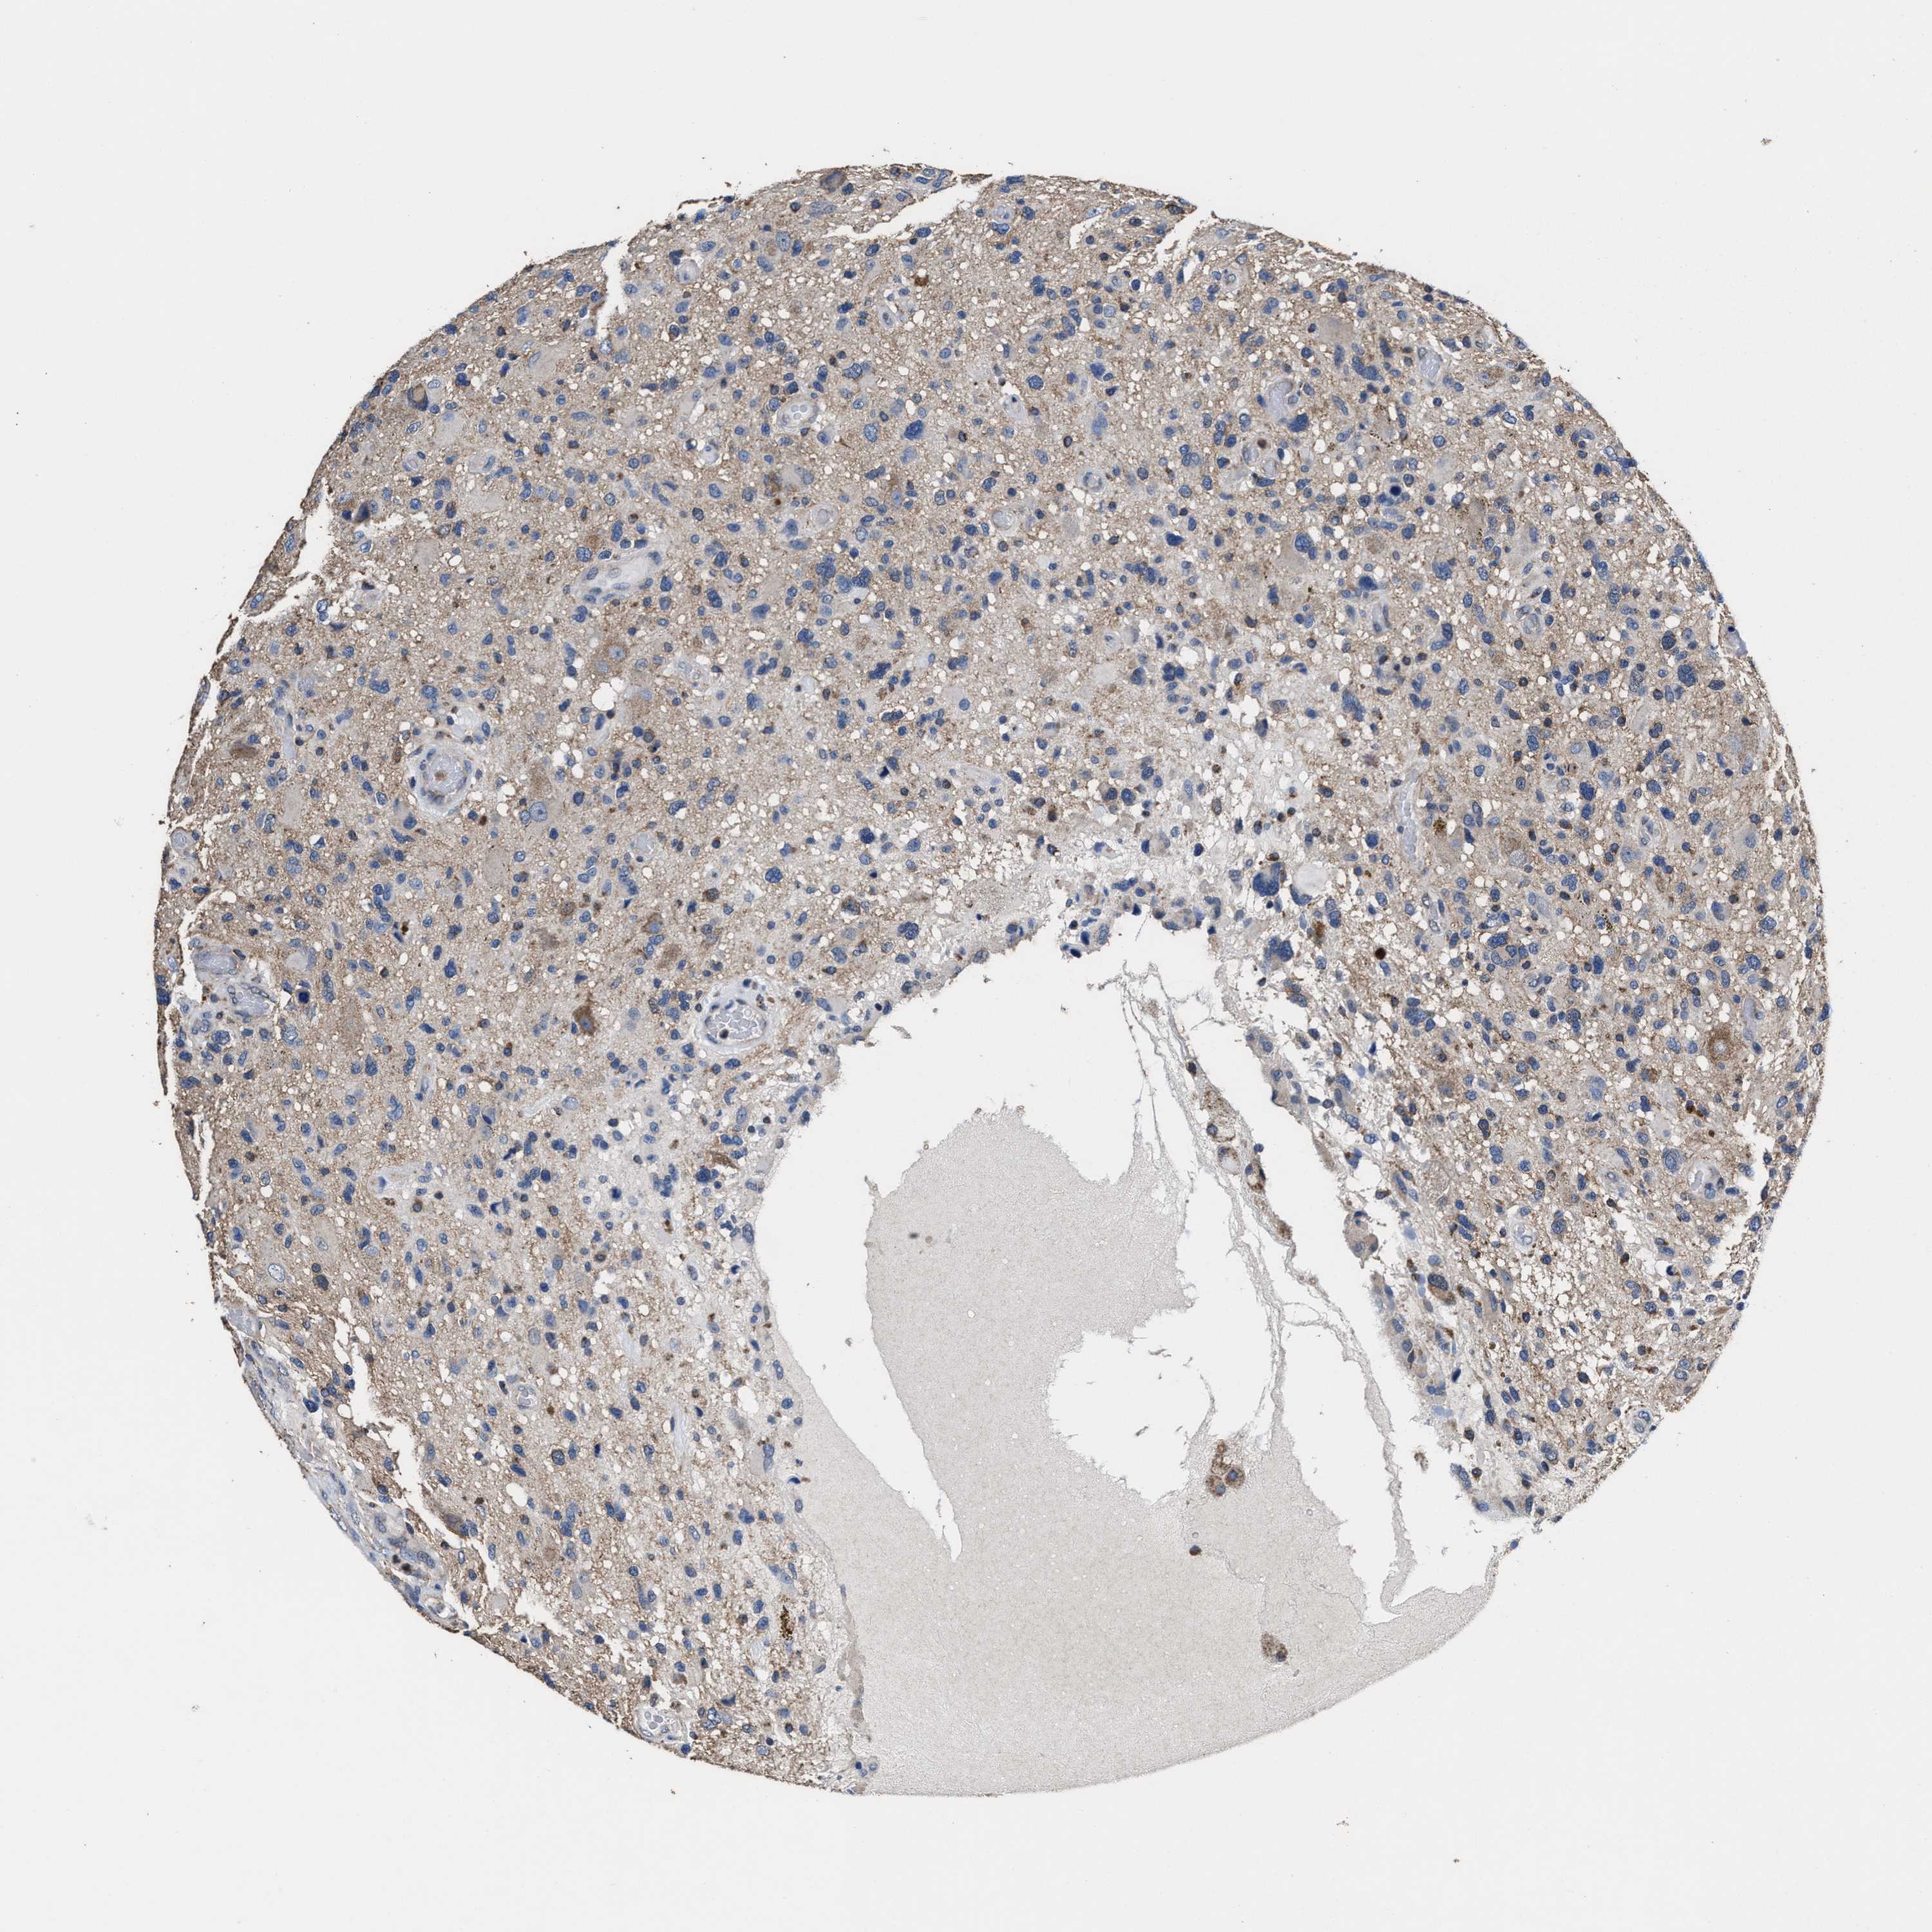

GLIOMA - Protein expressioni

A mouse-over function shows sample information and annotation data. Click on an image to view it in a full screen mode. Samples can be filtered based on level of antibody staining by selecting one or several of the following categories: high, medium, low and not detected. The assay and annotation is described here.

Note that samples used for immunohistochemistry by the Human Protein Atlas do not correspond to samples in the TCGA dataset.

Antibody stainingi

Antibody staining in the annotated cell types in the current human tissue is reported as not detected, low, medium, or high, based on conventional immunohistochemistry profiling in selected tissues. This score is based on the combination of the staining intensity and fraction of stained cells.

Each image is clickable and will lead to virtual microscopy that enables deeper exploration of all samples and also displays staining intensity scores, fraction scores and subcellular localization as well as patient and tissue information for each sample.

HPA022434

HPA022953

HPA022959

HPA028758

CAB007783

Glioma, malignant, High grade

Glioma, malignant, Low grade

Glioblastoma, NOS